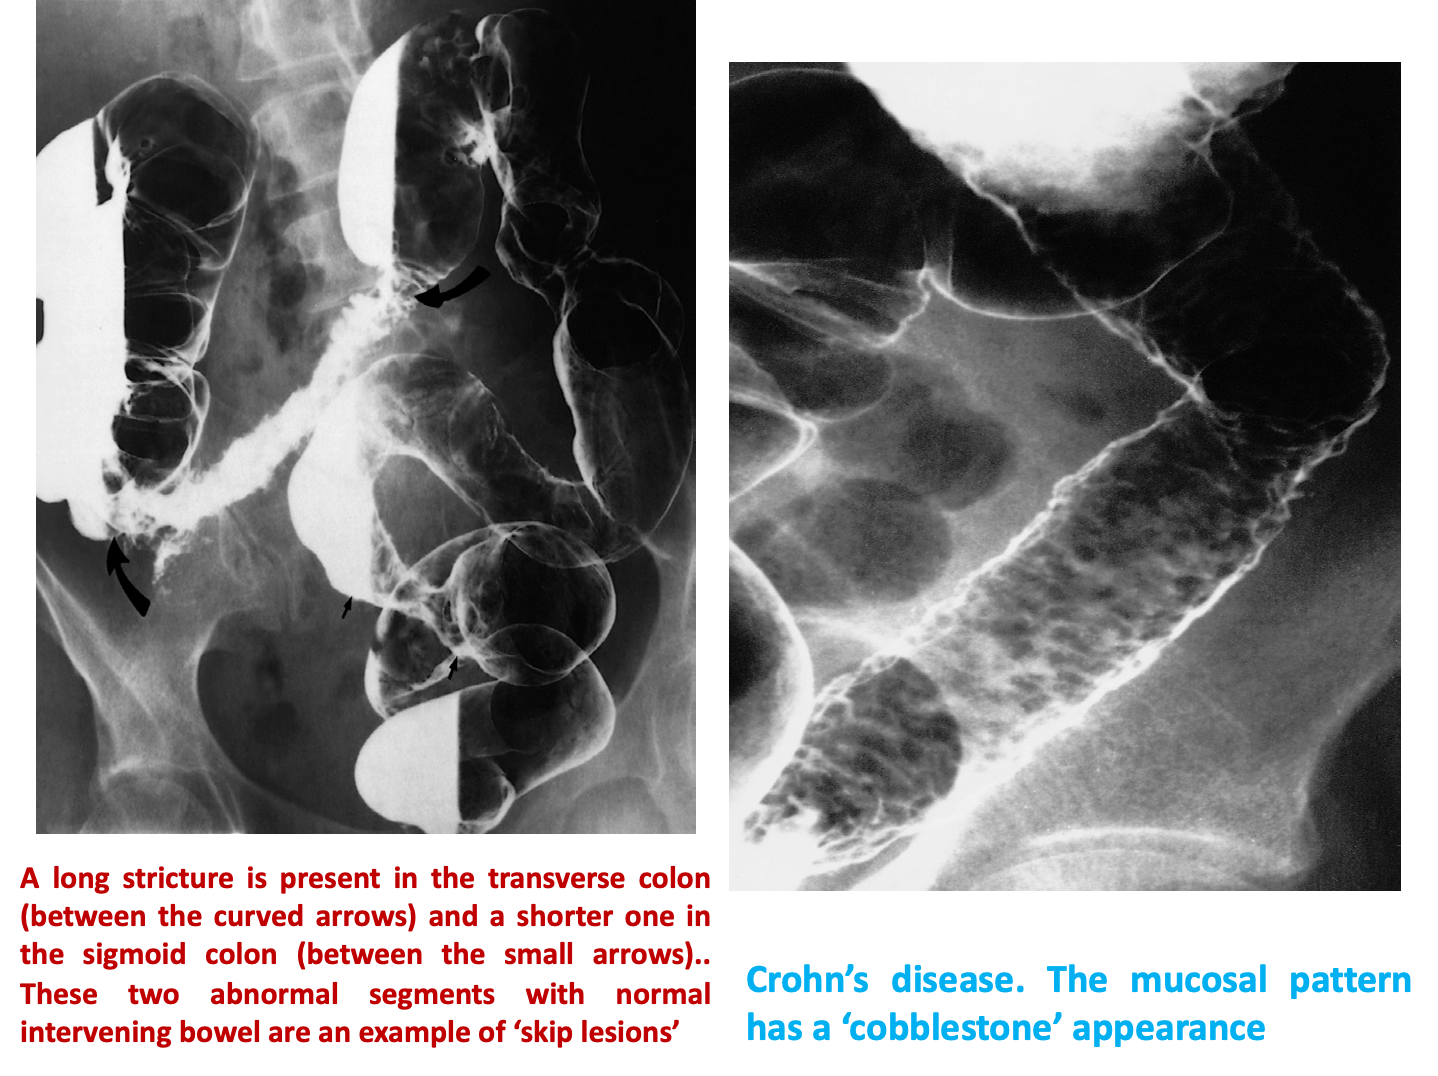

Note the normal mucosa on either side of the inflammatory stricture

Z It can affect any part of GIT but usually involve the small intestine specially the terminal ileum. Characteristic radiological features are

- skip lesion,

- aphthus ulcers,Â

- strictures,

- lymphadenopathy and

- fistula formation